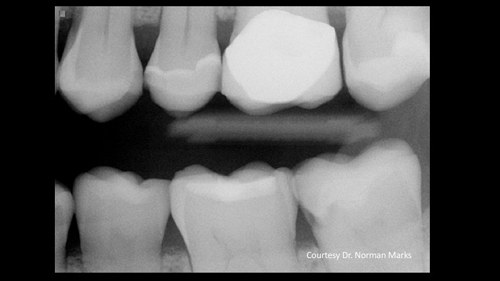

Figure 1: Current-generation bitewing digital dental radiograph shows some dental caries activity.

Recently, one of our practicing dentist team members who donates significant time to Clinicians Report Foundation and Practical Clinical Courses sent me a clinical example that frustrated both of us (figures 1 and 2). As you observe Figure 1, you will immediately see a lesion on the mandibular second molar and—perhaps—a small lesion on the maxillary first premolar. But do you see the lesion on the maxillary second molar? As you observe Figure 2, you are shocked to see the depth of the MO lesion that was not visible on the radiograph.

Figure 2: Obviously, the radiograph in Figure 1 did not show the major carious lesion.